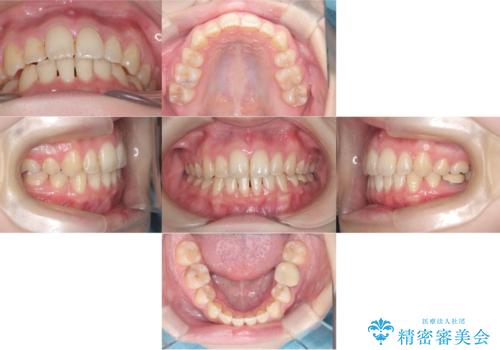

- 「歯のデコボコ、八重歯、口ボコが気になる」を主訴に来院された患者様です。

上下左右4番(4本)の歯を抜歯しワイヤー矯正で治療を行いました。

計4本の抜歯を行い、歯のデコボコと口元がすっきりし、大変ご満足していただけました。